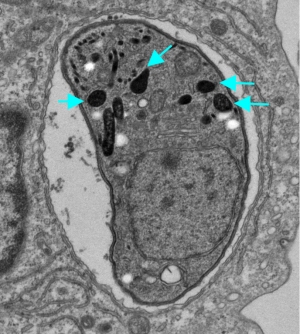

大阪大学の山本雅裕教授らによる研究グループは、トキソプラズマ症重症化は病原性因子GRA6によって宿主の免疫制御分子NFAT4を活性化し、宿主自然免疫細胞を強制的に利用(ハイジャック)することで引き起こされていることを明らかにした。

寄生虫トキソプラズマは全世界人口の3分の1が感染しており、健常者の場合は問題ないが、エイズ患者や抗癌剤投与下の患者には致死性の脳症・肺炎・心筋炎などを発症することが知られている。トキソプラズマは自然免疫細胞に潜伏して表面に出てこないため宿主免疫系の監視網を逃れることができるが、その詳細については明らかになっていなかった。

今回の研究では、トキソプラズマが感染細胞中に分泌するGRAタンパク質を哺乳動物細胞内で発現させ宿主転写因子活性化経路の反応を調べたところ、GRA6が免疫制御分子NFAT4を活性化していること、そしてNFAT4を強制的に活性化することで免疫細胞遊走能を有するケモカイン群を誘導し、感染局所に「トロイの木馬」となる好中球を遊走させて全身に感染拡大していくことが分かった。